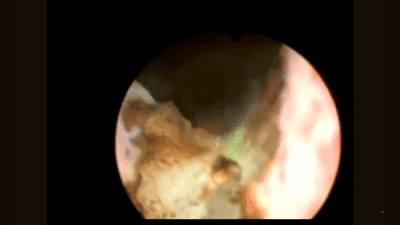

Tissue Sensor is a proprietary innovation by VPG LaserOne, developed to maximize safety during stone lithotripsy. It supports the global trend toward minimally invasive, endoscopic treatment of urolithiasis.

Tissue Sensor functions by identifying whether hard (stone) or soft (tissue) material is present in front of the surgical fiber tip. During lithotripsy, the laser automatically stops emission upon detecting soft tissue, effectively preventing mucosal injury and enhancing procedural safety.